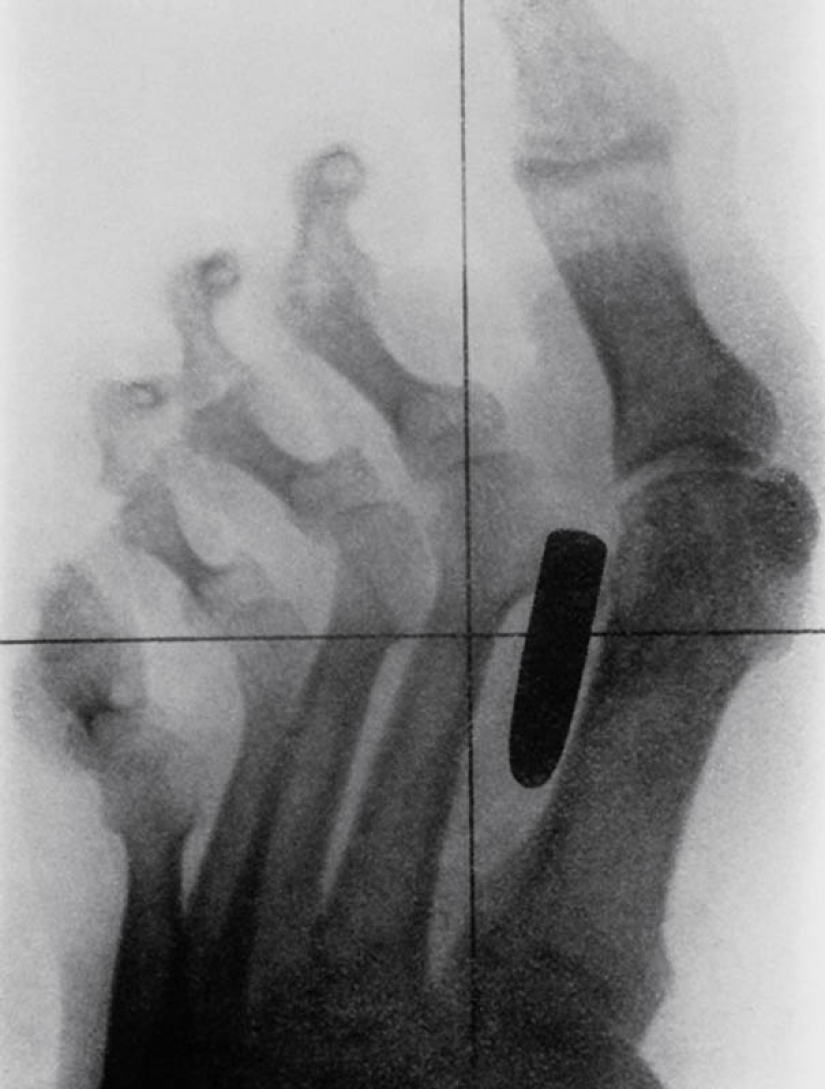

3. Vintage x-ray de el soldado de la guerra Anglo-Boer (1899-1902) con una herida de bala. La bala alojada en el metatarso entre el pulgar y el segundo dedo.